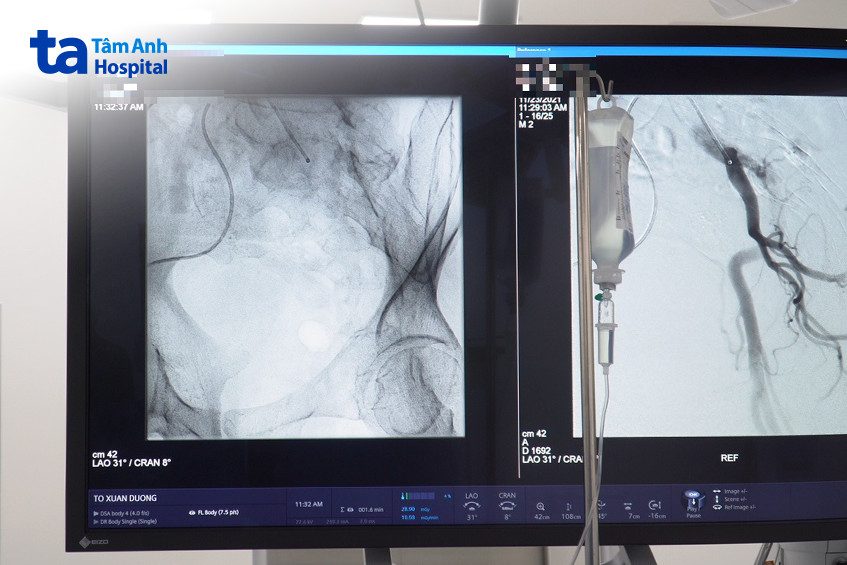

Nút mạch điều trị tăng sinh lành tính tuyến tiền liệt là phương pháp sử dụng ống thông siêu nhỏ đi trong lòng mạch máu, tiếp cận động mạch tuyến tiền liệt, sau đó bơm chất gây tắc để ngắt nguồn nuôi dưỡng khối u. Theo thời gian, khối u bị bỏ đói sẽ thu nhỏ thể tích, không còn chèn ép bàng quang và niệu đạo. Nhờ đó, các triệu chứng khó chịu tại đường tiểu như bí tiểu, tiểu nhiều lần, tiểu rắt… sẽ được cải thiện. Kỹ thuật được thực hiện bởi bác sĩ điện quang can thiệp với sự hỗ trợ dẫn đường của máy chụp mạch máu DSA.

Người bệnh nằm ngửa trên bàn can thiệp. Vùng da ở háng và đùi sẽ được sát khuẩn và phủ khăn vô trùng. Bác sĩ tiêm thuốc gây tê tại vùng bẹn, tạo một lỗ nhỏ trên da sau đó luồn vi ống thông (đường kính khoảng 1mm) vào trong lòng động mạch. Dưới sự dẫn đường của máy chụp mạch DSA, bác sĩ sẽ điều chỉnh ống thông để tiếp cận chọn lọc những nhánh mạch chịu trách nhiệm cấp máu cho tuyến tiền liệt.

Trong quá trình này, người bệnh có thể được tiêm thuốc cản quang để hỗ trợ điều hướng ống thông. Khi ống thông đã ở đúng vị trí, chất tắc mạch được bơm vào động mạch tuyến tiền liệt. Sau khi hoàn tất, bác sĩ rút ống thông ra khỏi động mạch và băng ép tại vị trí chọc kim để ngăn chảy máu. Thời gian can thiệp khoảng 30-45 phút, không tính thời gian chuẩn bị các dụng cụ can thiệp. Suốt quá trình can thiệp, người bệnh hoàn toàn tỉnh táo và trò chuyện được với bác sĩ, nhưng nhờ gây tê nên không có cảm giác đau đớn.

Do đó, kỹ thuật phải được thực hiện bởi các bác sĩ điện quang can thiệp giỏi và hệ thống máy chụp mạch hiện đại, độ phân giải tốt để tránh bỏ sót hoặc nút không chính xác khối u xơ tuyến tiền liệt.

Trung tâm còn sở hữu dàn phòng ốc, thiết bị can thiệp “khủng” với phòng can thiệp vô khuẩn tuyệt đối, hệ thống Robot chụp mạch máu Artis Pheno hiện đại bậc nhất, cho hình ảnh với độ phân giải cực đại, giúp bác sĩ nhìn rõ hệ mạch tiền liệt tuyến và thao tác chính xác. Phòng chăm sóc hậu can thiệp tiện nghi, sạch sẽ cùng đội ngũ điều dưỡng đông đảo, tận tâm giúp người bệnh được chăm sóc chu đáo, nhanh chóng hồi phục sức khỏe để sớm về nhà.